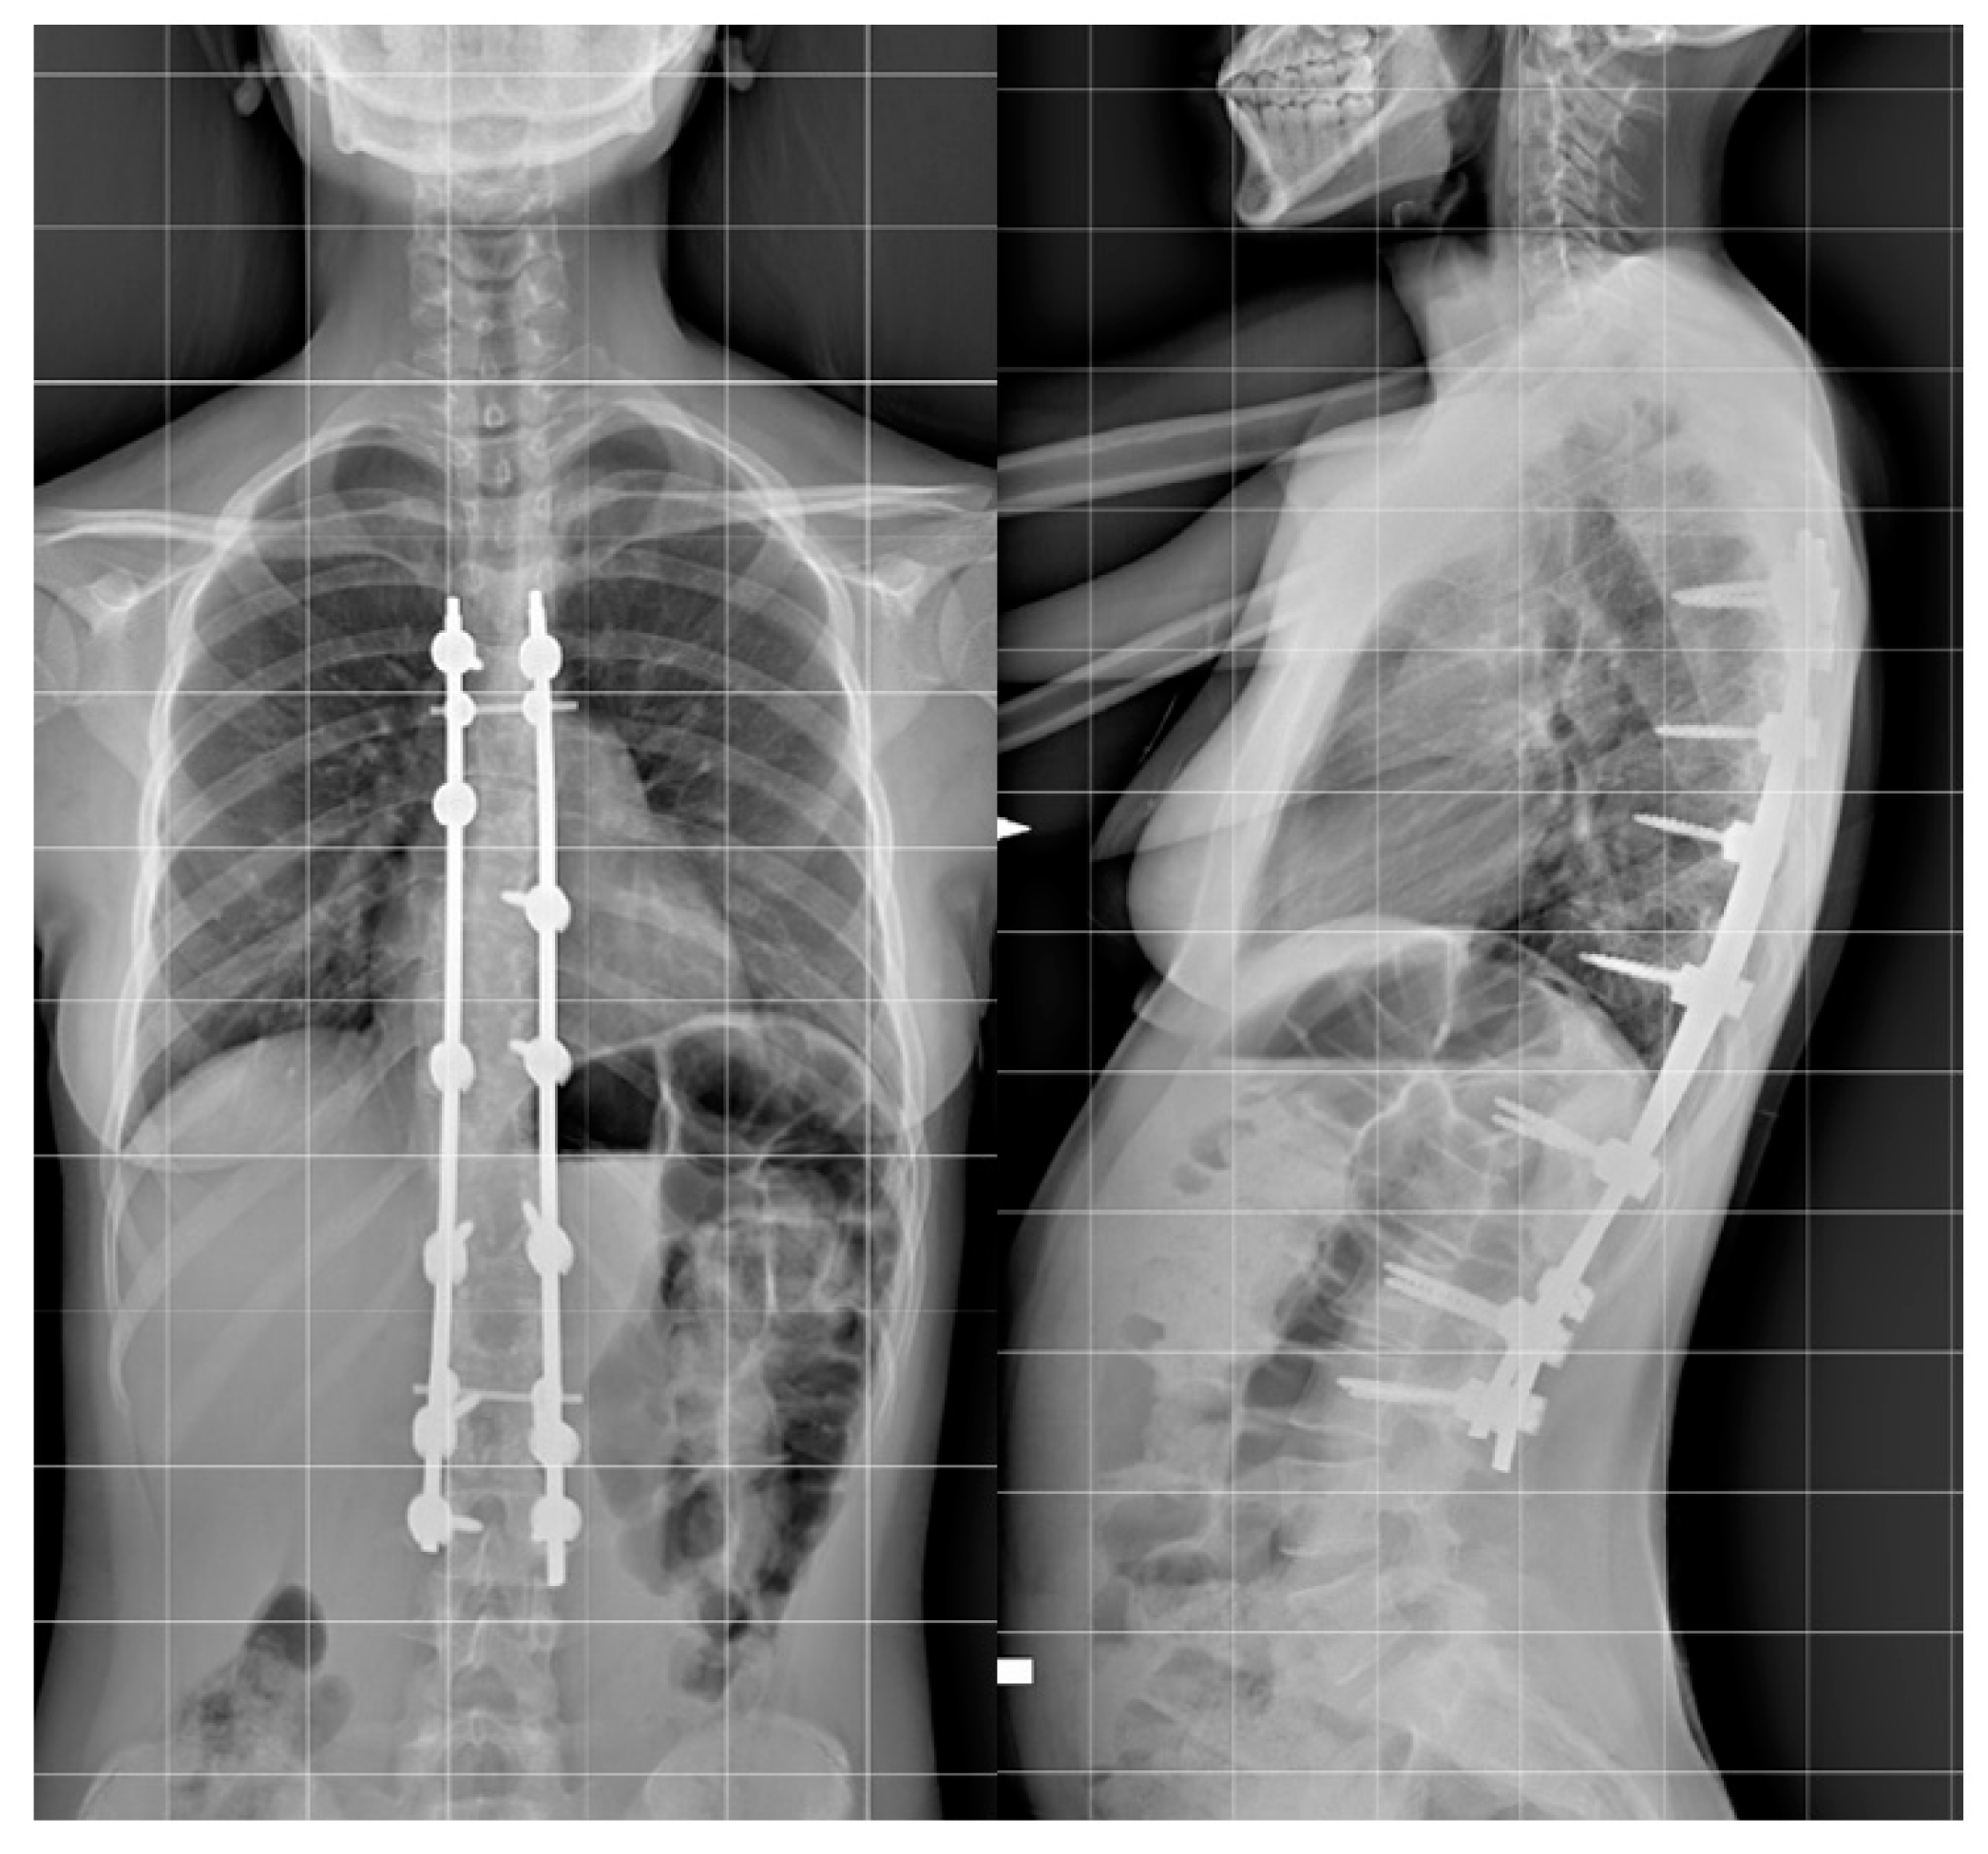

Step 2. Anchor point insertion: In the all-screw technique, titanium pedicel screws were inserted with the freehand technique with the assistance of C-arm fluoroscopy.(Figure 1).

Figure 1.

Example of all-pedicle screw construct for the treatment of AIS, AP, and LL.